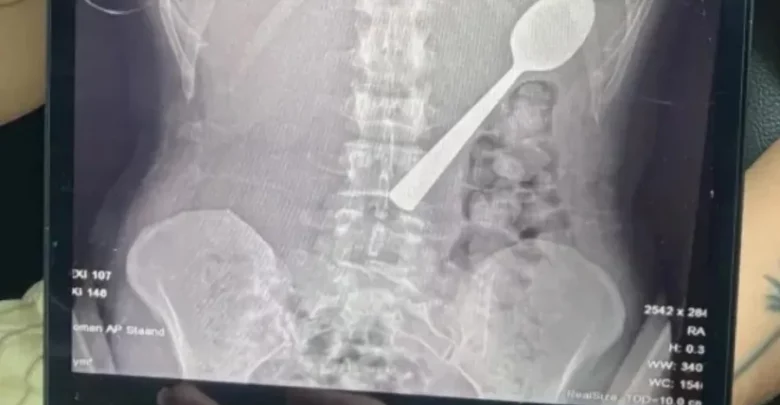

امرأة تبتلع ملعقة طولها 17 سنتيمتراً عن طريق الخطأ ..

حرير- تعرضت امرأة بلجيكية لموقف صادم بعدما ابتلعت ملعقة بطول 17 سنتيمتراً عن طريق الخطأ أثناء تناولها الطعام، وذلك بعد أن قفز كلبها على جسدها بشكل مفاجئ.

وقالت ريمي أملينكس، البالغة من العمر 28 عاماً، إنها اضطرت للاختيار بين الاختناق أو ابتلاع الملعقة، مشيرة إلى شعورها بأنها “انزلقت بسلاسة إلى معدتها”.

وأضافت في تصريحات صحفية أنها كانت تجلس على الأريكة أثناء تناول الزبادي، وعندما قفز كلبها من نوع “هنغاريان فيزلا” المعروف بنشاطه، تفاجأت بشكل كبير ما أدى إلى انحشار الملعقة في حلقها بالخطأ، فحاولت إزالتها بيدها، لكن الموقف كان سريعاً جداً ولم يكن أمامها سوى ابتلاعها لتجنب الاختناق.

وبعد تناول العشاء، أدركت خطورة الموقف، وذهبت إلى الأطباء الذين أبلغوها أن الملعقة كبيرة جداً لتخرج طبيعياً، ما استدعى انتظار إجراء منظار معدة.

وأُزيلت الملعقة بعد يومين تحت التخدير الموضعي، حيث اضطر الأطباء لتدويرها داخل المعدة، ما تسبب في نزيف بسيط، وأكدت ريمي أن الحادث لم يترك أي أضرار دائمة، لكنها تعرضت لالتهاب في الحلق ونزيف في المعدة طفيف وحساسية لبعض الوقت.